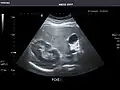

Kidneys: Right and left kidneys measure 11.5 cm and 12 cm in length respectively. No hydronephrosis. Small left lower pole kidney cyst.

Right kidney -